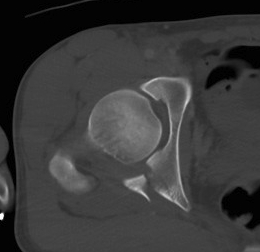

CT

Configuration

1-2 mm sections

CT reconstruction

- remove head to view acetabulum

- beware volume averaging

- used to guide surgery

Diagnose

Loose bodies

Femoral head fractures

Subtle subluxation

Articular steps

Roof arc measurement